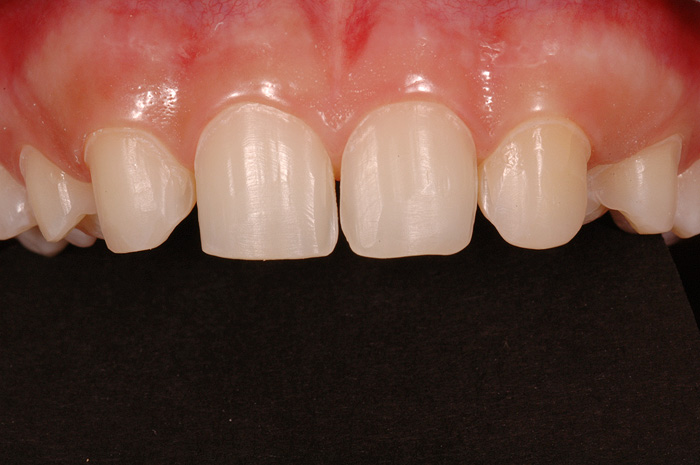

Ist ein Zahn sehr stark oder bis unter das Zahnfleisch zerstört, kann er nicht mehr mit einer herkömmlichen Kunststofffüllung versorgt werden. Der noch vorhandene Restzahn lässt sich nur noch durch eine Krone restaurieren. Sie besteht aus einem individuell gegossenen Metallgerüst, auf welches in mehreren Schichten Keramik aufgebrannt wird oder kann als rein vollkeramische Krone hergestellt werden, was zu einer noch höheren Ästhetik führt.

Die Restauration eines Zahnes mit einer Krone ist aufwendig. In einem ersten Schritt wird Karies und das alte Füllungsmaterial vollständig entfernt und der Zahnstumpf wieder aufgebaut. Eine präzise Abformung der Situation dient dem Zahntechniker als Grundlage für ein Gipsmodell, auf dem er die Krone herstellt. Sofern Farbe und Form perfekt stimmen, kann die Krone in einer zweiten oder dritten Sitzung beim Zahnarzt zementiert werden. Für die Zeit zwischen Präparation des Zahnes und dem definitiven Zementieren der Krone wird der Zahn mit einem individuell hergestellten Provisorium versorgt.